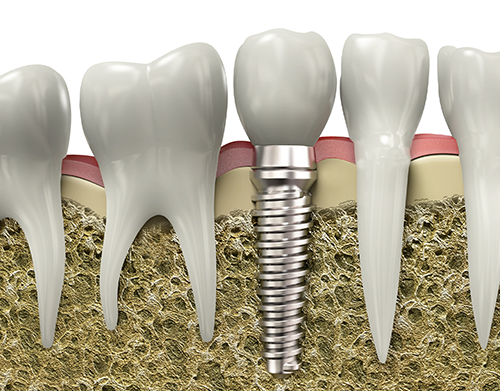

İMPLANT

Doğal dişlerin herhangi bir nedenle kaybedilmesi durumunda, kaybedilmiş olan doğal dişlerin yerine uygulanan titanyum vidalardır. Kemik içine yerleştirilen bu vidalar, belli bir iyileşme süresi içinde kemik ile bütünleşir ve üzerlerine yapılan sabit ya da hareketli protezlere destek olurlar. Böylece hastanın yaşam kalitesi artırılarak, sosyal olarak kendilerini daha güvende hissetmesi sağlanır. Doğal diş eksikliğinin giderilmesinde kullanılan en sağlıklı yöntemdir.